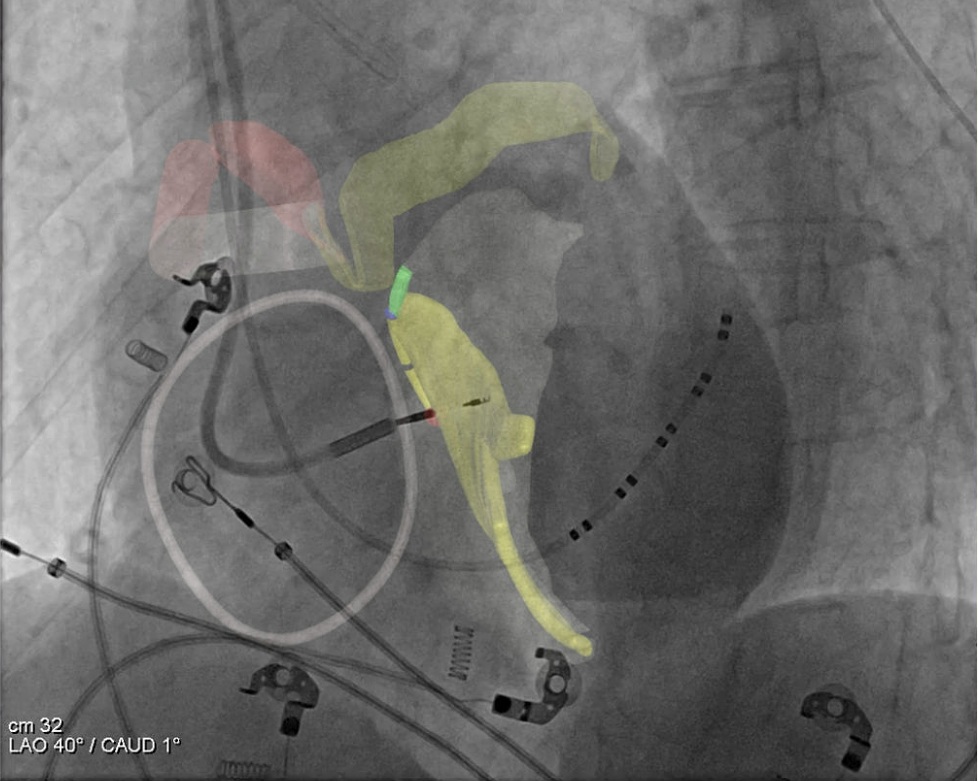

The CARA system integrates two core components—the CARA Metis Simulator and CARA Atlas Navigator. The CARA Metis Simulator is a preprocedural planning software that utilises CTA-based anatomical landmarks to identify the cardiac conduction axis and generate a personalised 3D map of the patient’s cardiac conduction system. CARA Atlas Navigator is an intraprocedural guidance platform that overlays the patient-specific conduction system model generated by the Metis onto live fluoroscopic images to assist physicians during image-guided interventions.

The CARA system operates on a standard workstation platform, integrates with existing fluoroscopy systems, and does not have direct patient contact. The system utilises advanced image processing and artificial intelligence (AI)/machine learning (ML)-based algorithms to support CT segmentation, fluoroscopic metadata extraction, and catheter detection, with all outputs subject to physician review and confirmation.